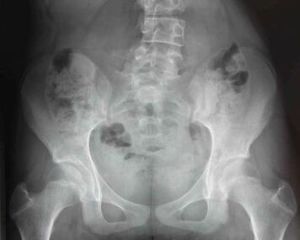

病因及常見疾病

鈣化灶鑑別診斷